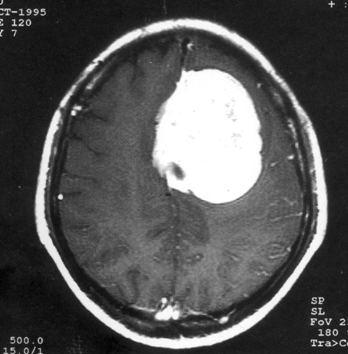

问题 病历摘要:??患者,男,40岁。发作性左下肢抽搐1年余,每次发作3~5分,每周发作1~2次。每次发作后感左下肢乏力,约半日后可自行恢复。既往身体健康。体检:神清,头顶部偏右有局限性骨性隆起(1.5×1.5cm),左鼻唇沟稍浅,伸舌居中。感觉、运动无明显异常。左浅反射减退,左下肢腱反射稍亢进,左Babinski征(-)。 可选择下列哪些检查帮助诊断